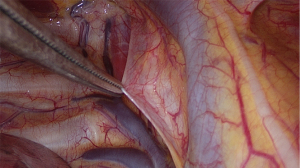

The SVI VATS procedure has been previously published (20). This section briefly summarises the procedure. First, a short-acting muscle relaxant (mivacurium) was introduced, to insert the double-lumen endotracheal tube. During the relaxation period, surgical incisions were made on the right side, as per routine practice, after local infiltration with 2% lidocaine. Subsequently, the following surgical incisions were made: a 3-cm utility incision in the mid-axillary line, a 1-cm submammal fold incision for the camera, and a 5-mm incision for the instrument between the submammal fold and sternum. To block the cough reflex, 5 mL of 0.5% bupivacaine was administered near the right vagus nerve (Figures 1-3), and 4–5 mL was administered between two and five intercostal nerves close to the spine (paravertebral blockade) (Figure 4). After elimination of the short-acting muscle relaxant (mivacurium), the patient breathed spontaneously without coughing, and in some cases, 4–6 positive end-expiratory pressure (PEEP) was administered to maintain perfect oxygenation. During MG, complete thymectomy was performed by removing the thymus and perithymic fatty tissues. As a routine procedure, the right pericardium-diaphragm angle fat, aortocaval groove, and aortopulmonary window fat were removed. Phrenic nerves were identified on both sides. The innominate vein was visualised, and all horns of the thymus were dissected immediately into the neck. Additionally, accessory horns, commonly under the innominate vein, were routinely examined and were not overlooked. The thymus was then dissected up to the left phrenic nerve, which was identified after opening the left pleura using a 30° viewing-angle optical camera. Anaesthesia provided pressure support ventilation (PSV) when the left side was opened, although inspiration and expiration were managed by the spontaneous ventilation of the patient alone (20). The specimen was placed in an Endobag and removed from the thoracic cavity through an axillary incision. At the end of the operation, a 28-Fr chest tube was inserted through a 10-mm port into the operated area.